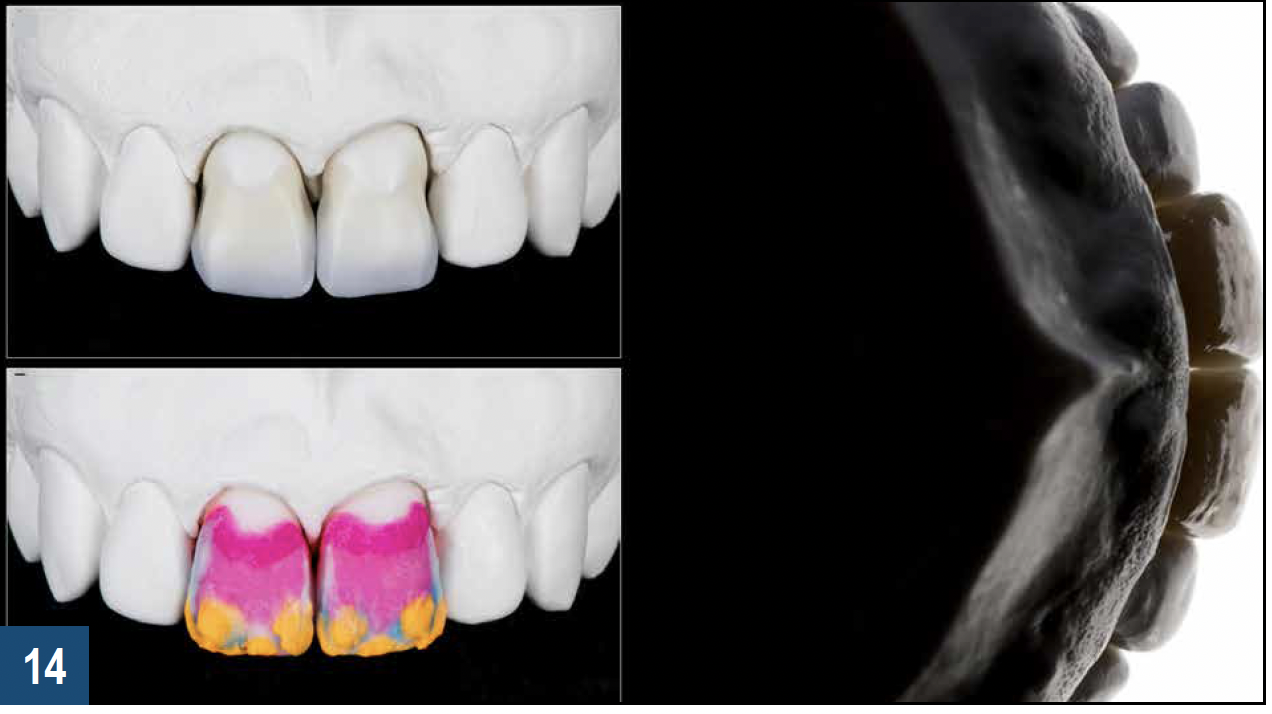

When a patient presents with previously restored nonvital anterior teeth (Figure 12), the challenge to produce a satisfactory esthetic outcome becomes a collaborative effort shared between the clinician and the dental labora-tory team. The darkened stumpf and subgingival root structure may produce an unfavorable shade to any definitive translucent ceramic restoration. In addition to its usefulness in intact nonvital teeth, the walking bleach technique with 10% carbamide peroxide is a safe and effective treatment modality for teeth with denuded enamel. Treatment to achieve the desired final shade may be completed within a single in-office application; however, the decision to discontinue internal bleaching will largely depend on the ceramist's abilities and knowledge of the materials being applied to mask the final stumpf shade of the tooth preparation (Figure 13 and Figure 14). Residual oxygen from the decomposition of 10% carbamide peroxide may remain within the dental tissues for 7 to 15 days after internal bleaching.39,40 This excess oxygen has the potential to negatively impact the bond strength of the adhesive components during the cementation of the final crowns, and it is therefore recommended that at least 2 weeks elapse before final delivery of the definitive restorations (Figure 15).41

Fig 13. Left panel: Darkened tooth stumpfs and root structure may impact the esthetics of any translucent ceramic restorations placed over them. Right panel: Internal bleaching has been shown to be an effective means of producing a more favorable substrate color that favors the achievement of an optimal esthetic final result.

Figure 13

Fig 14. The final stumpf shade should ultimately be guided by the ceramist’s knowledge of core materials (top left panel) and layering porcelain for masking the underlying tooth structure (bottom left panel).

Figure 14

Fig 15. Final delivery of full-contour porcelain crowns on the central incisors in the patient shown in Figure 14. For restorations that will be adhesively luted over internally bleached teeth, a minimum waiting period of 2 weeks should be observed to allow the dissipation of excess oxygen that may otherwise negatively impact the bond strength of the cement.

Figure 15